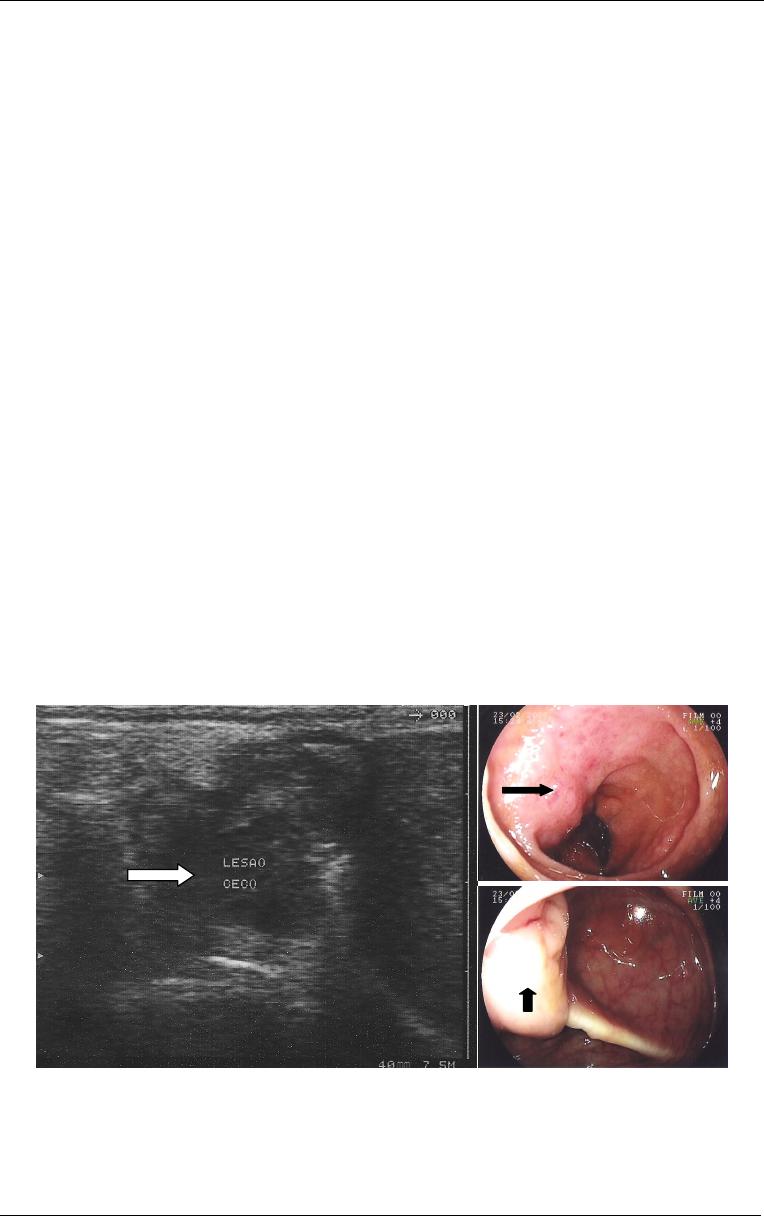

endometriose peritoneal (Kennedy et al, 2005) (Figura 8). divergências na

Figura

8

-

Imagem de

ultrassonografia transvaginal

evidenciando espessamento da

camada muscular própria de

segmento intestinal (seta)

decorrente de endometriose

intestinal. Obs: Imagem cedida

pelo Dr. Manoel Orlando

Gonçalves do Laboratório de

Análises Clínicas Gastão Fleury

S/C Ltda.

Figura 6

- Imagem de

colonoscopia com deformidade

em sigmóide (seta) decorrente de

endometriose intestinal. Observa-

se mucosa levemente congesta.

Obs. Imagem cedida pelo Dr.

Lucio Rossini.

7

em reto (seta) decorrente de

se mucosa intestinal normal.